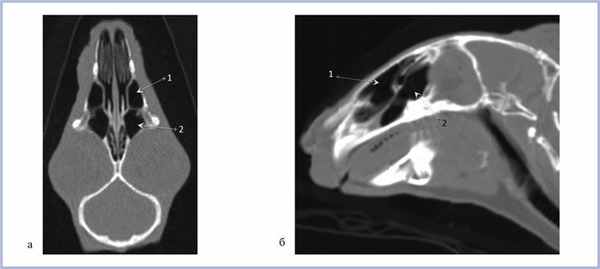

Верхнечелюстная пазуха у кролика делится на 3 широко сообщающиеся между собой полости, располагающиеся одна над другой [2]. С полостью носа верхнечелюстная пазуха сообщается через соустье, расположенное впереди решетчатой кости (рис. 1) [17].

Рис. 1. Полость носа и верхнечелюстные пазухи взрослого кролика.

На рис. 2 представлены верхнечелюстные пазухи кролика в возрасте 3 нед в различных проекциях; на рис. 3 в возрасте 6 мес. Таким образом, у кроликов уже в возрасте 3 нед определяются сформированные верхнечелюстные пазухи.